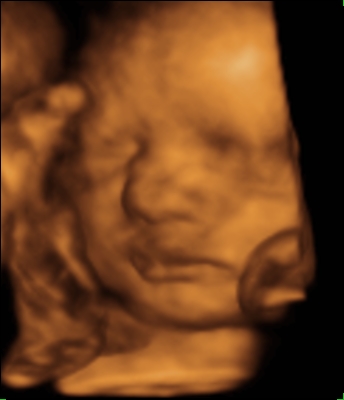

Nagyon ügyes ez a Saskia lány. Teszel fel róla képet? És rólad nagypocisat?